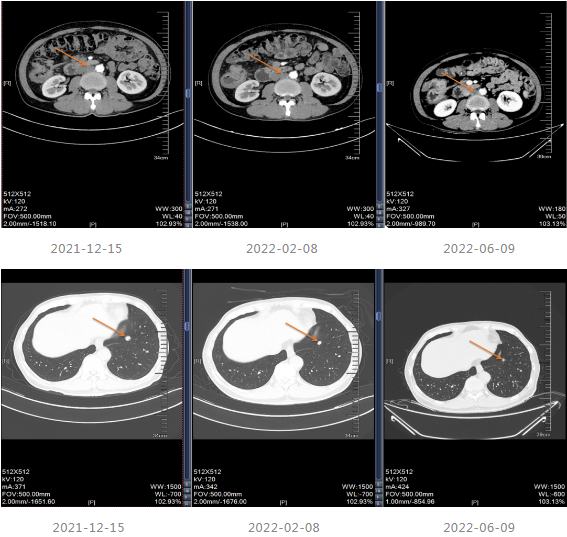

2021-12-15影像学复查提示疾病进展。

2021-12-20至2022-03-21更改化疗方案,采用“贝伐单抗+FOLFOX6方案”进行治疗。

2022-04至2022-07采用“贝伐珠单抗联合卡培他滨”维持治疗4周期,维持治疗期间患者渐感腹胀伴消瘦。